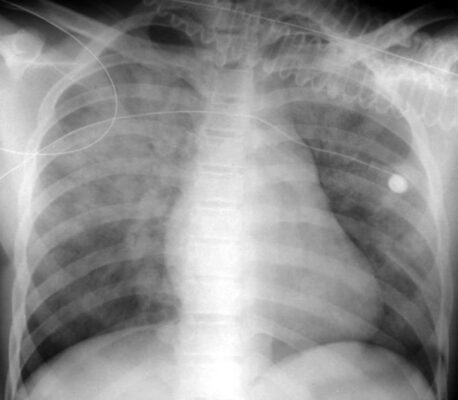

- Bệnh khoang chứa khí có thể phân bố khắp phổi, như trong phù phổi (Hình 1), hoặc có thể khu trú hơn, như trong bệnh viêm phổi thùy hoặc phân thùy (Hình 2).

Phù phế nang phổi (Pulmonary alveolar edema)

- Phù phế nang phổi cấp tính điển hình thường tạo ra bệnh lý khoang chứa khí hai bên, quanh rốn phổi, đôi khi được mô tả là có hình dạng cánh dơi (bat-wing) hoặc cánh thiên thần (angel-wing) (Hình 6).

- Biểu hiện có thể không đối xứng nhưng thường không chỉ một bên. Phù phổi có nguồn gốc từ tim thường phối hợp với tràn dịch màng phổi và chất dịch làm dày các rãnh lớn và rãnh bé.

- Bởi vì chất dịch không chỉ lấp đầy các khoang chứa khí mà còn cả các phế quản, nên thường không có hình ảnh phế quản chứa khí trong phù phế nang phổi. Thường thì phù phổi hết nhanh sau khi điều trị (<48 giờ).